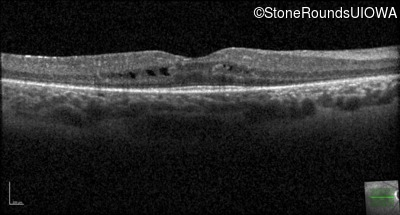

Optical Coherence Tomography - Right - 20/40 -2

Exemplar / OCT Stack